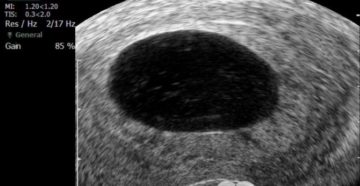

Анэмбриония – беременность есть, или ее, все же, нет? К сожалению, далеко не все наступившие…